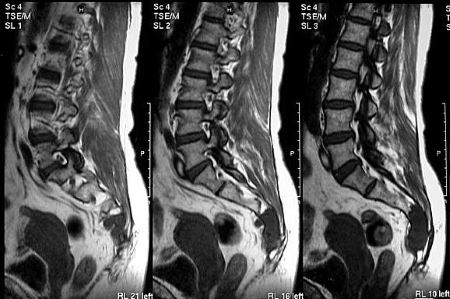

Опухоль на МРТ.

Спондилолистез на МРТ.

МРТ, УЗИ

С помощью УЗИ можно диагностировать патологии опорно-двигательного аппарата на ранней стадии развития. Исследование проводится для оценки состояния кровеносных сосудов, расположенных около копчика и в органах малого таза. УЗИ — самая безопасная диагностическая процедура, позволяющая с высокой точностью обнаружить опухоли и воспалительные процессы в брюшной полости.

На полученных при МРТ изображениях отчетливо визуализируются мягкие, хрящевые, костные структуры. Диагностическая манипуляция часто используется при неинформативности других процедур.